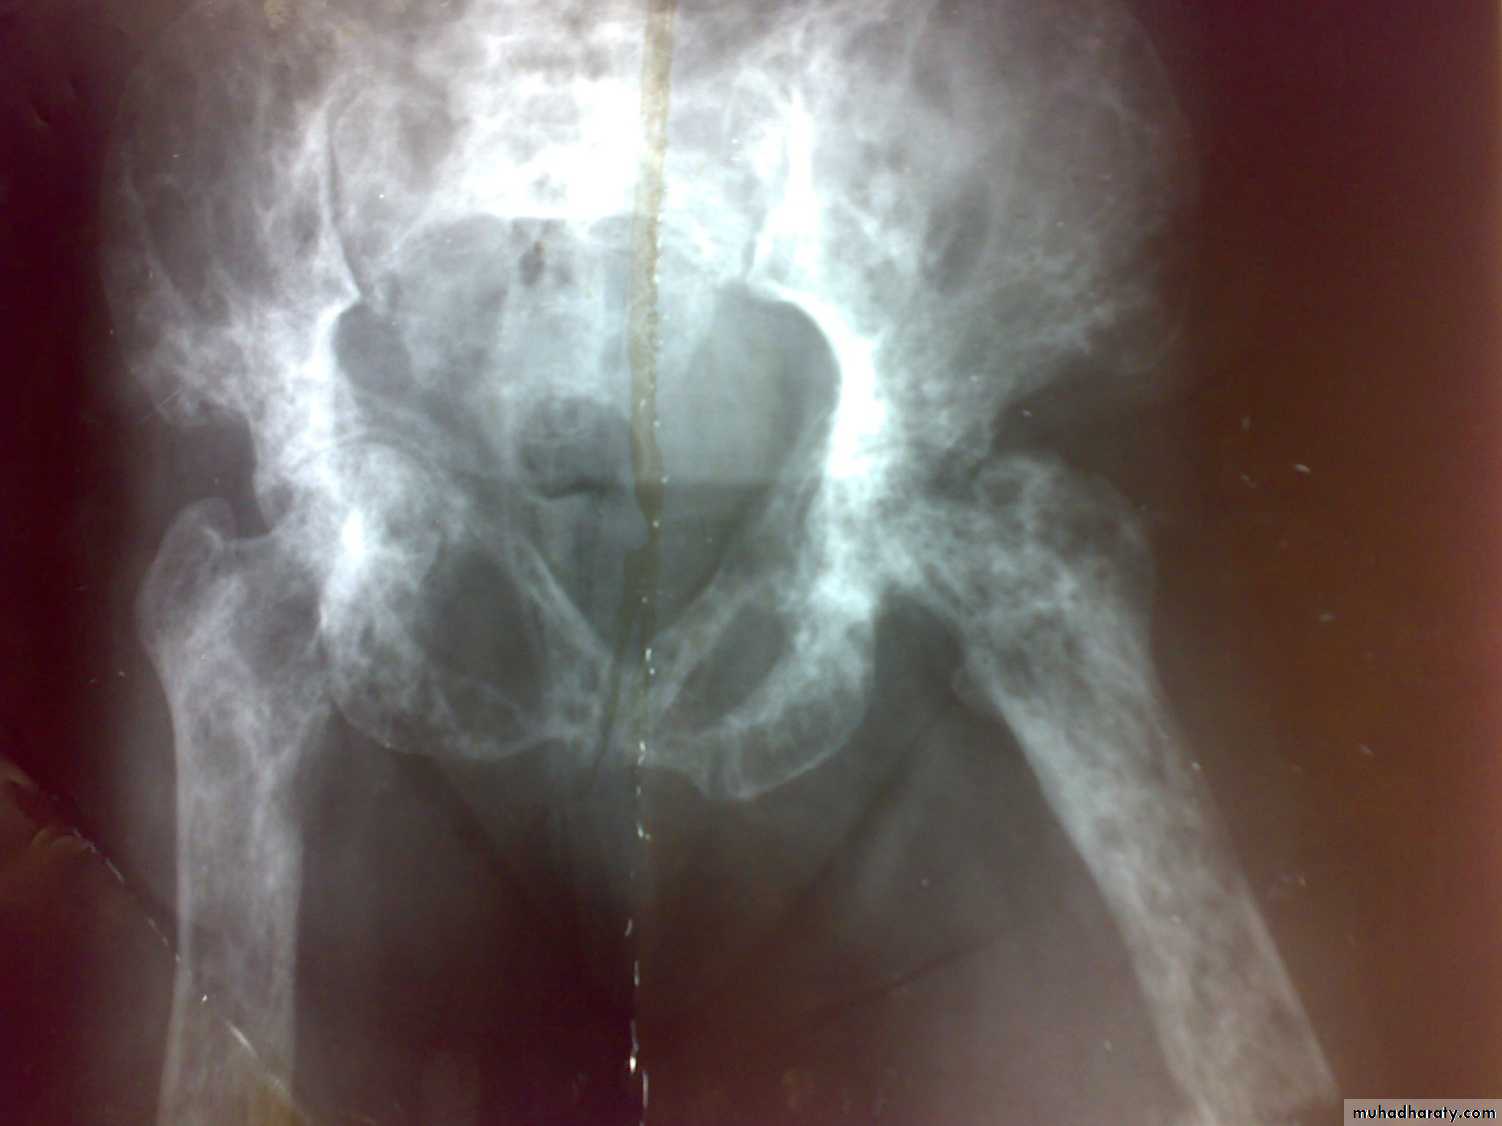

Paget’s disease

This disease characterized by increased bone turnover and enlargement and thickening of bone, but internal architecture is abnormal and bone is usually brittle.Paget’s disease

Complications1- fractures.

2- osteoarthritis

3- nerve compression and spinal stenosis.

4- bone sarcoma.

5- high cardiac output failure.

6- hypercalcaemia in immobilization.